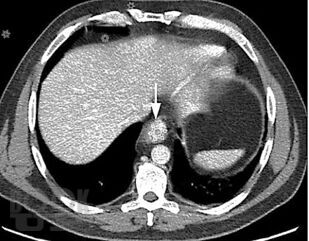

В учебном пособии представлена современная информация об эпидемиологии, классификации, клинике, диагностике, принципах и результатах лечения рака желудка. Особое внимание уделено перспективным методам первичной и вторичной диагностики рака пищевода.